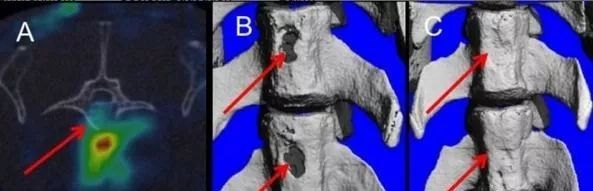

实验室的研究人员给予实验动物对象为期 21 天的甲状旁腺激素注射,同时使用取自成年人骨髓 5 个单位的干细胞注射。结果表明,联合治疗可以显著增强干细胞的迁移到骨折部分,并且促进骨折处形成新的、健康的骨骼(图 1)。

图1 A 干细胞靶点的脊柱骨折;B 两个脊椎骨折;C 干细胞与甲状旁腺素治疗 8 周后修复的脊柱